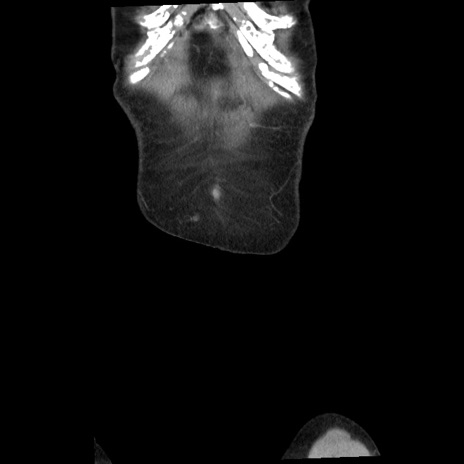

横断像